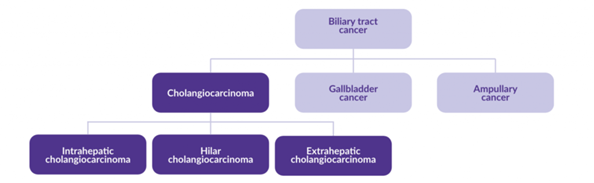

Afhankelijk in welk deel van deze galwegen de galwegkanker zich ontwikkeld, wordt het opgedeeld in 3 types en 2 hoofdgroepen:

- Intrahepatisch (liggend in de lever)

Intrahepatisch (perifeer) galwegkanker (cholangiocarcinoom, iCCA).

Ontstaat in de (kleinere) galwegen die in de lever liggen. - Extrahepatisch (liggend buiten de lever)

- Hilair of Perihilair galwegkanker (cholangiocarcinoom, pCCA of ook wel Klatskin tumor):

- Ontstaat net buiten de lever, daar waar de linker en rechter galwegtakken van de lever bij elkaar komen.

- Distaal galwegkanker (cholangiocarcinoom):

- Ontstaat ergens in de hoofdgalweg welke loopt van de lever naar de 12-vingerige darm (duodenum).

Andere vormen van kanker van het galwegsysteem zijn galblaaskanker en Papil van Vater kanker. Hier gaat deze folder niet verder op in.

Figuur 2: Classificatie van galweg kanker types. Bron: website AMMF.org.uk/about/cholangiocarcinoma 10-1-2023